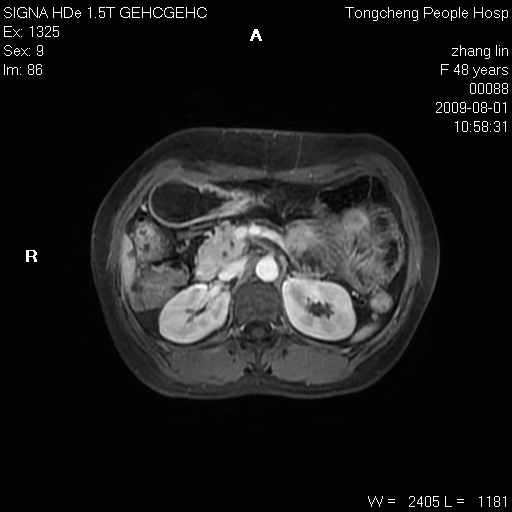

女,48岁。健康体检,彩超发现右肾占位性病变。平素健康。

临床诊断:右肾占位性病变,性质待定(囊肿?肿瘤?)。

上中腹部mr平扫+增强扫描,图像如下:

右肾上极见一类圆形病灶,t1wi呈等信号t2wi呈等高混杂信号,三期增强无强化,边界清---考虑囊肿出血。

同反相位均表现为等信号,病变无强化,考虑含蛋白的囊肿可能,弥散加权相或许有些帮助,

慢性胆囊炎